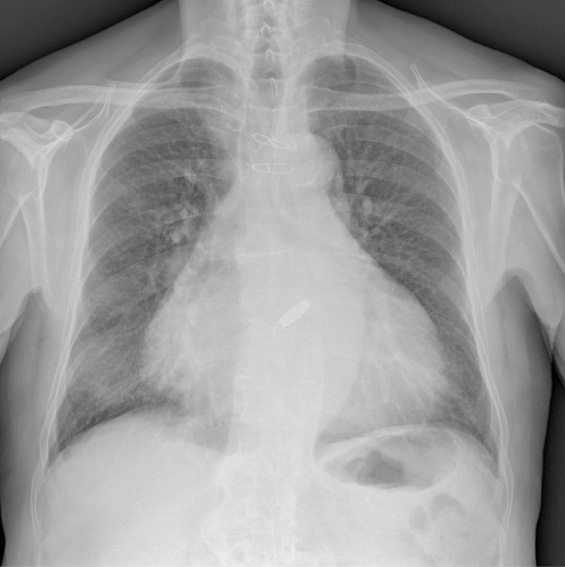

L’Rx torace in quell’occasione risultava negativo per focolai pleuro-parenchimali (Figura 1).

Figura 1. Rx torace (anno 2010): cardiomegalia, legacci metallici contro lo sterno, protesi valvolare, aortosclerosi